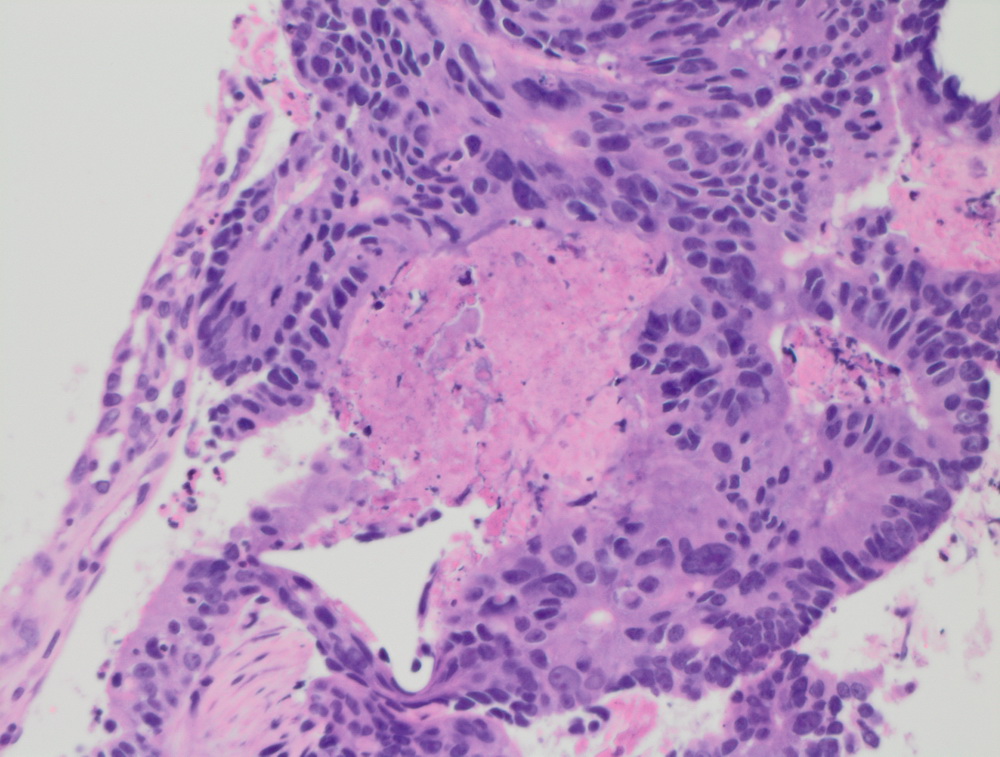

Окрашенные срезы под микроскопом

Неспецифический рак молочной железы. Участок in situ карциномы внутри протока, криброзного типа. |

Низкодифферинцированный рак пищевода. |